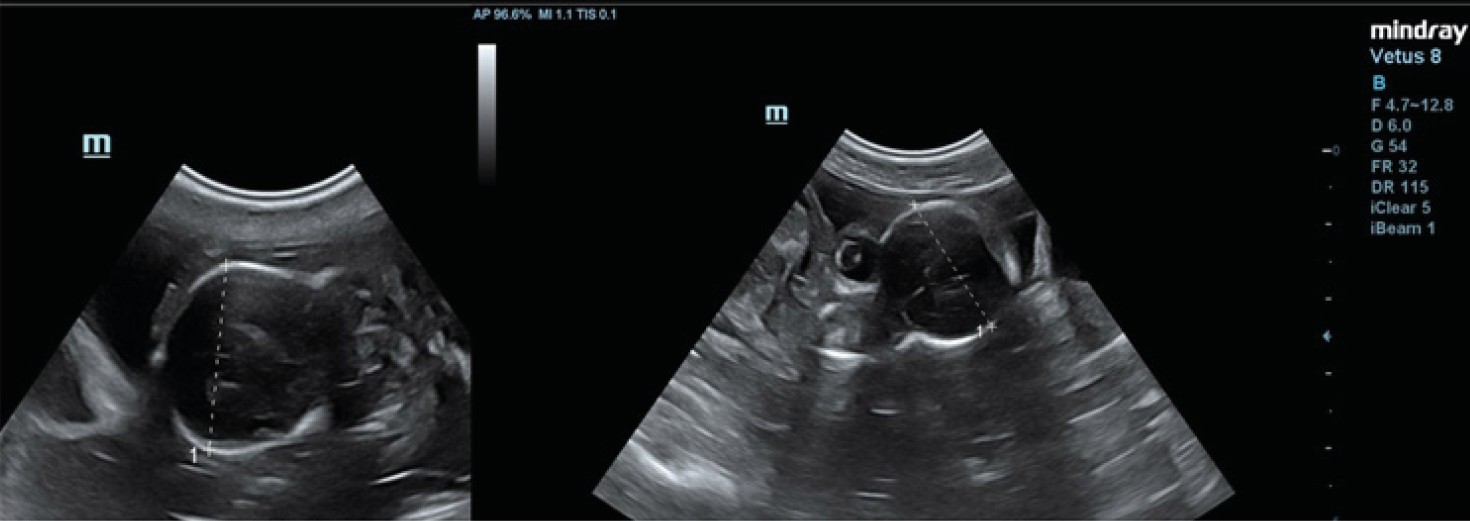

Fig. 1. Ultrasound image reflecting the biparietal diameter of a French bulldog on the 58th day of pregnancy

Source: compiled by N.I. Kolyadina, A.V. Shumeyko on the Mindray Vetus 8 Ultrasound Machine.